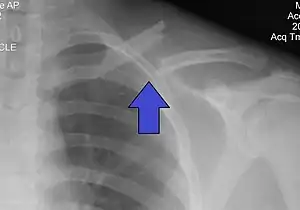

| X-ray of a left clavicle fracture | |

The basic method to check for a clavicle fracture is by an X-ray of the clavicle to determine the fracture type and extent of injury. In former times, X-rays were taken of both clavicle bones for comparison purposes. Due to the curved shape in a tilted plane X-rays are typically oriented with ~15° upwards facing tilt from the front. In more severe cases, a computerized tomography (CT) or magnetic resonance imaging (MRI) scan is taken. However, the standard method of diagnosis through ultrasound imaging performed in the emergency room may be equally accurate in children.[5]